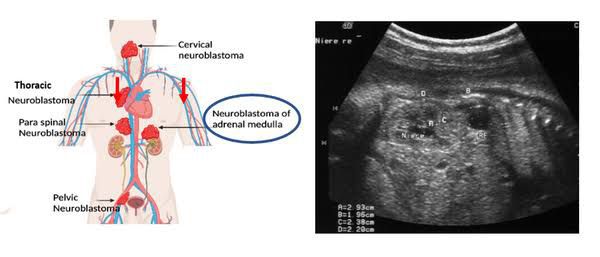

Neuroblastoma is a cancer that develops from immature nerve cells found in several areas of the body. Neuroblastoma most commonly arises in and around the adrenal glands, which have similar origins to nerve cells and sit atop the kidneys.